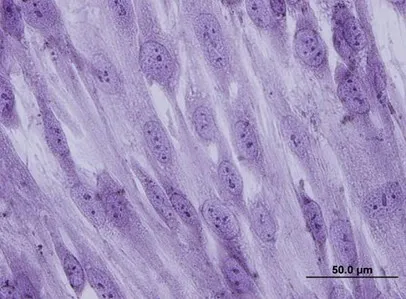

피부 장벽을 넘어 심장 근육, 미세 혈관 및 간 세포 재생 메커니즘 성공 (논문 73, 75, 76)

18. 첨단 조직 공학(Tissue Engineering)을 위한 생체 적합 지지체 고도화

Phan TT*, I Lim, H Huynh, BH Bay, ST Lee, MT Longaker. Differences in collagen production between normal and keloid-derived fibroblasts in serum media cocultured with keloid-derived keratinocytes. Journal of Dermatological Science 2002; 29(1): 26-34

17.